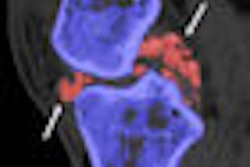

Dr. Tim Bongartz and colleagues from the Mayo Clinic in Rochester, MN, wanted to test DECT's accuracy for detecting gout using a scanning technique modified to detect intra- or periarticular monosodium urate (MSU) deposits.

Eighty participants (half with confirmed gout; half without gout who underwent the standard test for other reasons) underwent dual-source DECT (80 and 140 kVp) scanning of the aspirated joint (Somatom, Siemens Healthcare), and the images were classified by a musculoskeletal radiologist as positive or negative for MSU deposition.

The sensitivity and specificity of DECT for diagnosing gout was 93% and 95%, respectively. There were three false-negative results, all in patients without a history of gout who were experiencing their first flare-ups.